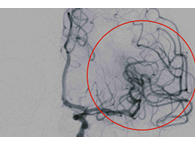

救1人救全家!治療腦中風快1秒多救3萬個腦細胞

腦中風是造成成人殘障的主要原因,年齡愈大發生的機會愈高...

北部南下彰化訪友的42歲女子小惠(化名),與友人交談中竟突發急性缺血性腦中風...

彰基醫學中心及時救治 青壯年腦中風患者三起

隨著氣溫驟降,彰基醫學中心在同一天接連收治了三名約40歲左右的青壯年腦中風患者。...